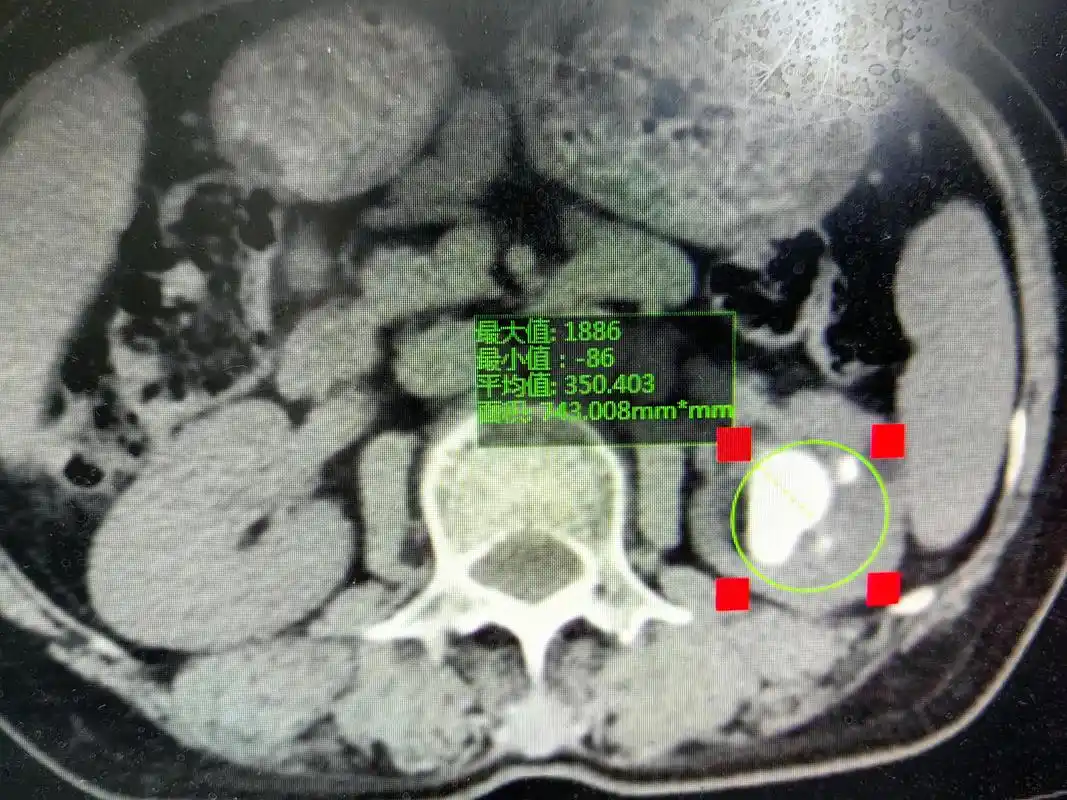

肾结石的硬度已经颠覆了医生的认知,肾结石的ct值了解一下

泌尿系统结石之肾结石ct表现